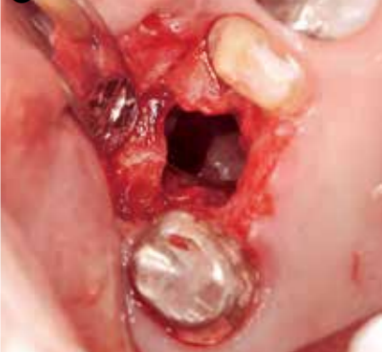

在穿孔直径大的情况下(有牙冠大小),无法获得自然闭合(图5),所以要马上转诊到专科医生处做修补手术。

图5 16牙冠大小的穿孔。可以看到窦内有掉入的牙齿。由于穿孔直径很大,取出掉入的牙根后,必须做修补手术